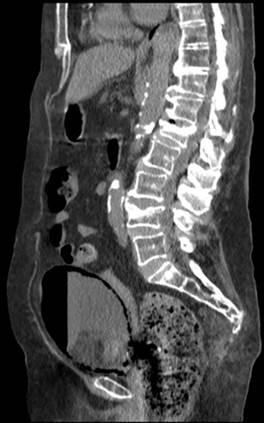

TC abdominal sin contraste: Pequeño derrame pleural bilateral con colapso pasivo del pulmón subyacente. Hígado, vías biliares, páncreas, bazo, suprarrenales sin alteraciones. Riñones seniles con hidronefrosis bilateral grado I. Aorta abdominal ateromatosa con ligera dilatación de 25 mm a nivel infrarrenal. Severa presencia de gas entre la pared de la vejiga, con nivel hidroaéreo en su interior en relación con cistitis enfisematosa. Marcado fecaloma en ampolla rectal y divertículos en sigma sin signos de complicación. Pequeña cantidad líquido libre intraabdominal (Figura 3).

Se objetiva hipodensidad en toda la pared parietal vesical así como en las porciones más anteriores a nivel intraluminal correspondiente con aire.

Figura 3 Reconstrucción TC corte sagital